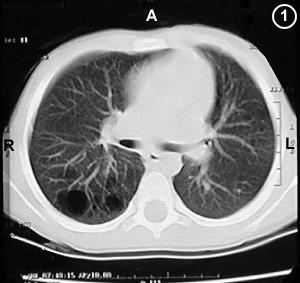

Corte Tomográfico " 1 "

Corte nivel inferior a la carina de traquea:

Parenquima pulmonar lado derecho inferior, note las estructuras redondeadas oscuras también otras mas pequeñas, los quistes o sáculos característicos en el parenquima correspondiente al segmento apicalis del lóbulo pulmonar inferior derecho.